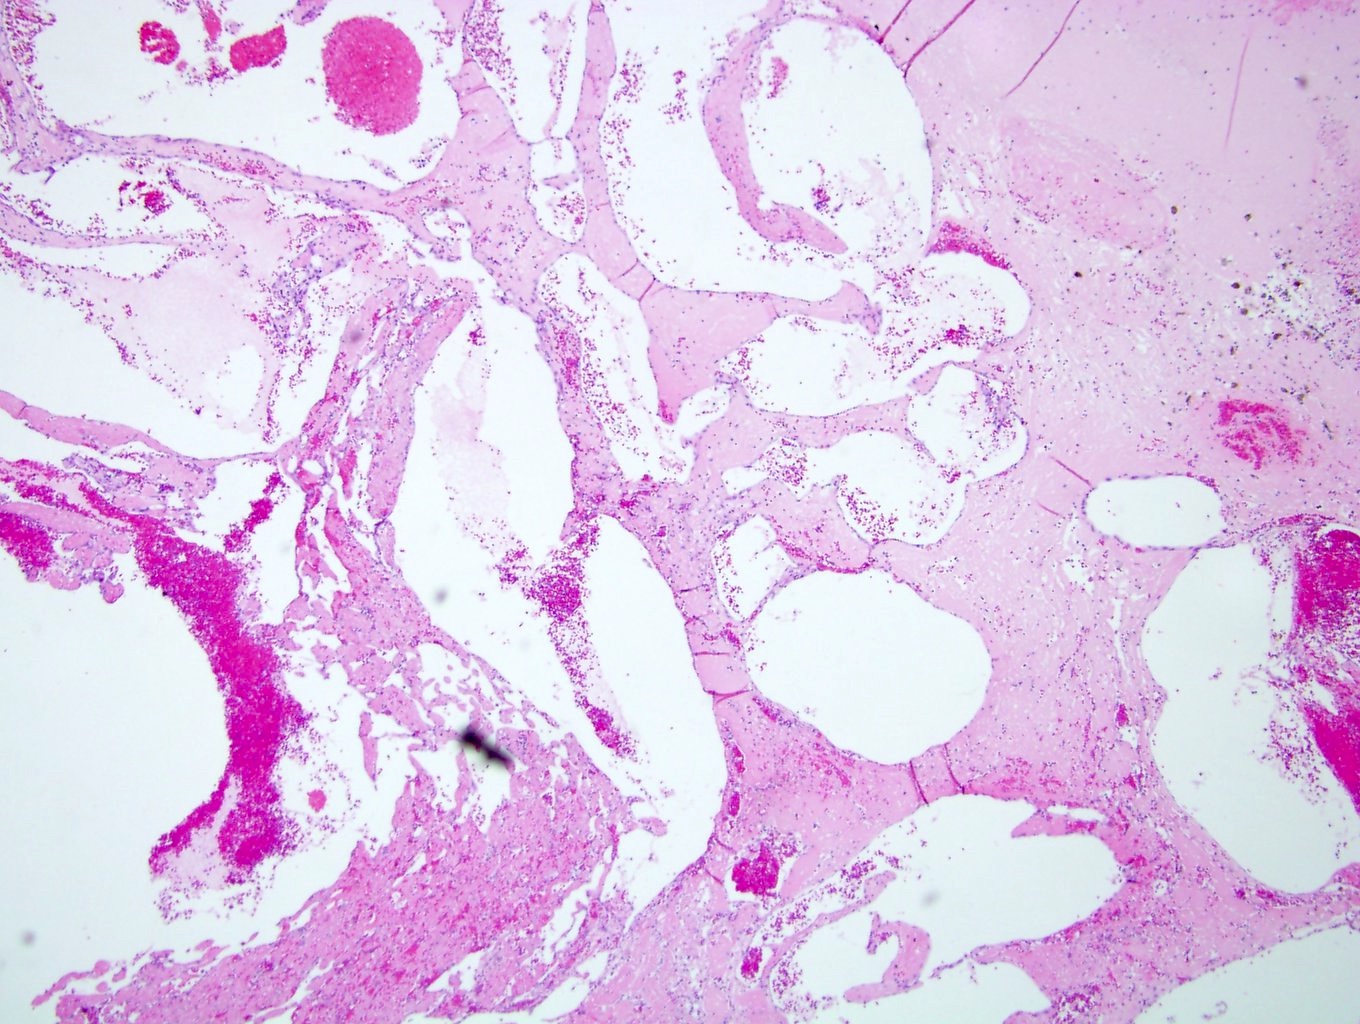

Microscopic (histologic) description

- Circumscribed, unencapsulated proliferation of irregular, blood filled vascular spaces lined by a single layer of endothelial cells

- May or may not show lobular growth pattern with large feeding vessels at periphery (Virchows Arch 2012;461:669)

- Multiple subtypes:

- Capillary: more common, characterized by slit-like vascular spaces

- Cavernous: characterized by dilated vessels

- Mixed: features of both capillary and cavernous

- Anastomosing hemangioma (variant of capillary)

- Anastomosing hemangioma (AH):

- Capillary sized sinusoidal vessels with anastomotic arrangement

- Scattered hobnail endothelial cells

- Extramedullary hematopoiesis, fibrin thrombi, extensive perirenal fat entrapment, intravascular growth and mast cells may be seen (Histopathology 2014;65:309)

- Cytologic atypia and mitotic activity rare

- Regressive changes, including hyalinization, cystic changes and fatty overgrowth (Histopathology 2014;65:309)

Microscopic (histologic) images